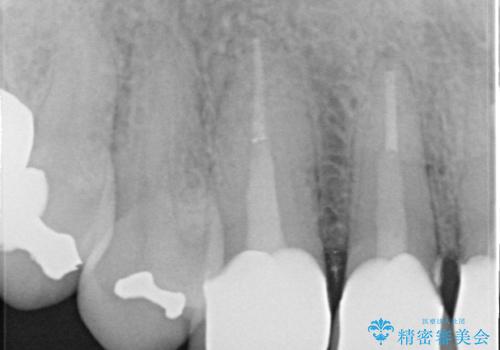

- 以前治療した上の前歯の不自然な保険のかぶせ物を自然なものにしたいとのことで来院されました。

右上の前から1番目から3番目までの歯のかぶせ物を土台から再治療することとなりました。

金属の土台を、ファイバーコアという歯根にやさしく白いものに交換して、かぶせ物をオールセラミックにしました。